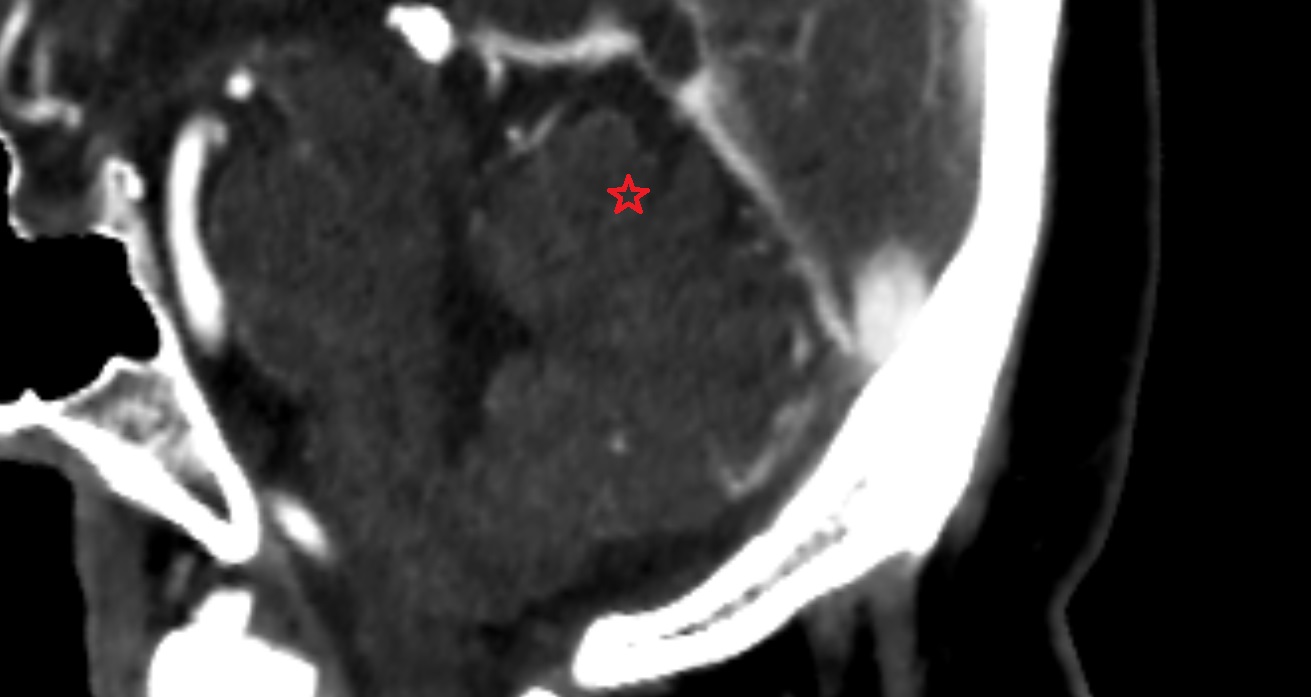

- Heart